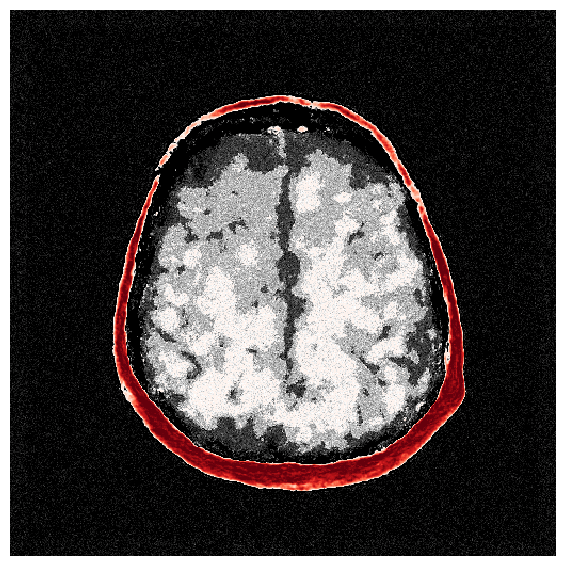

4.3 Traditional amortized inference

To illustrate the limitations of amortized VI, we train a CNF on pairs without evoking iterative improvements by ASPIRE. We emphasize that the observations are the raw unsummarized waveforms similar to that shown in Figure 6. Training details are included in Section \thechapter.C. After training by minimizing Equation 3, the CNF with weights , provides an amortized approximation of the posterior, , from which we can sample (cf. Equation 4). The results, shown in Figure 7, demonstrate that the samples from , for an unseen test observation, , lack distinct features beyond an unrealistic skull and unresolved internal tissue structure. A comparison of these samples and the posterior mean, , in Figure 7 with the ground truth, Figure 7, highlights the poor quality of this approximation. Note, throughout this exposition we calculate the posterior statistics (i.e. mean and standard deviation) over samples, please consult the Section \thechapter.E for a discussion on this quantity. This experiment underscores the challenge of directly learning the probabilistic inverse mapping from the acoustic data to the velocity parameters, a difficulty previously noted in the literature [63]. This challenge is often referred to as the ‘end-to-end’ problem [64]. We address this problem with the score-based summary statistic employed by ASPIRE.